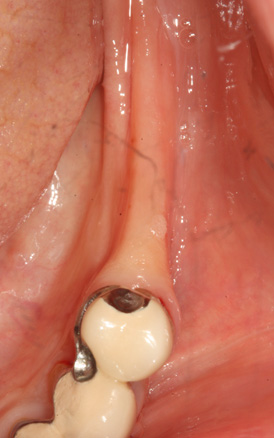

청담네오플란트 원데이 임플란트

하루만에 발치와 임플란트 식립을 동시에!

일반적으로 살릴 수 없는 치아를 발치하면, 2~3개월의 잇몸뼈 회복기를 거친 후 임플란트를 식립하게 됩니다. 하지만 잇몸뼈의 소실이

심하지 않은 경우 임플란트의 전체 치료기간 단축과 환자분의 불편감을 최소화하기 위해 내원 당일 발치 및 임플란트 식립을 진행할 수 있습니다.

필요에 따라 치조골 이식이 필요할 수 있으며, 가능한 경우 당일 임시 보철물 장착까지 해드려 심미적 기능을 회복할 수 있습니다.

발치 후 임플란트를 식립하고, 바로 임시 보철물을 제작함으로써 일상생활에서 불편감을 최소화할 수 있습니다.